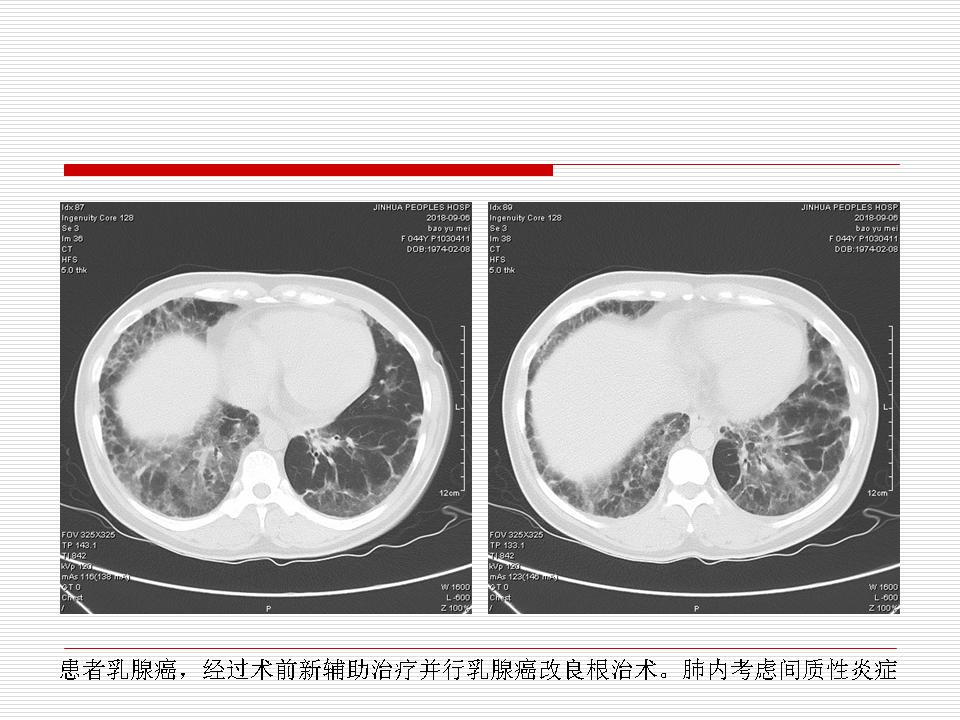

肺部阴影永恒且最重需要鉴别的是:到底是炎症还是肿瘤?但临床的病例中的影像表现难以界定或有些肿瘤特征,同时又有些炎症特点是非常常见的情况。作为临床医生我们怎么去总结分析,并找到之所以是炎症或之所以是肿瘤的细微差别或特点非常重要,也非常有用。2019.12.7浙江省2019年胸心外科学学术年会在宁波召开时,我的临床病例分析与经验总结<那些像肺癌的炎症与像炎症的肺癌>获得在大会交流的机会,以下为该PPT的内容,与你分享,希望对同道有益,有借鉴与启迪。若有探讨与进一不完善的建议,欢迎文末留言讨论: